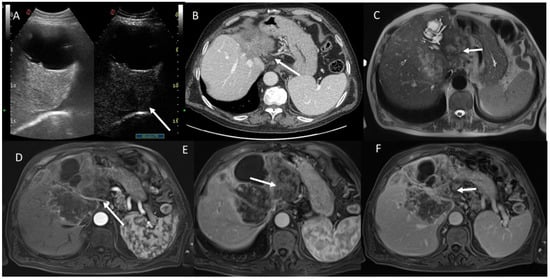

- Granata, V.; Fusco, R.M.; Catalano, O.; Filice, S.; Avallone, A.; Piccirillo, M.; Leongito, M.; Palaia, R.; Grassi, R.; Izzo, F.; et al. Uncommon neoplasms of the biliary tract: Radiological findings. Br. J. Radiol. 2017, 90, 20160561. [Google Scholar] [CrossRef] [PubMed]